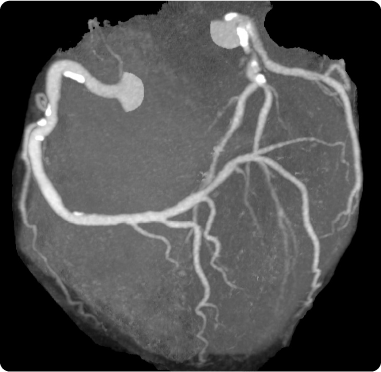

冠動脈の狭窄が徐々に進行した場合には狭心症となりますが、冠動脈が突然閉塞してしまった場合には急性心筋梗塞となります。この様に、狭心症と心筋梗塞はいずれも冠動脈の動脈硬化が進行して発症する病気であり、両者をひとくくりにして、虚血性心疾患と呼ぶこともあります。 虚血性心疾患は、日本でも高齢化や食生活の欧米化によって患者数が増加しています。 当院では、心疾患を疑う患者さんが初めて受診された場合、まずは心電図、胸部レントゲン写真、心エコー検査、ABI検査を施行します。しかし、狭心症の場合、発作を起こしている際中(症状がある時)には、心電図や心エコー図検査にも異常が認められるのですが、症状が治まってしまうと正常に戻ってしまうことも多いため、これらの検査だけでは診断がつかないこともあります。

このような場合には、心臓のマルチスライスCTを施行し、画像として直接冠動脈を観察します。CTで冠動脈の狭窄が疑われる場合には、手首や足の付け根から細い管を挿入して、冠動脈を造影する心臓カテーテル検査を行って、治療方針を決定します。当院は、清田区で唯一の心臓マルチスライスCTと、心臓カテーテル検査を行っている病院です(2019年7月現在)。

虚血性心疾患のCTアンギオグラム画像